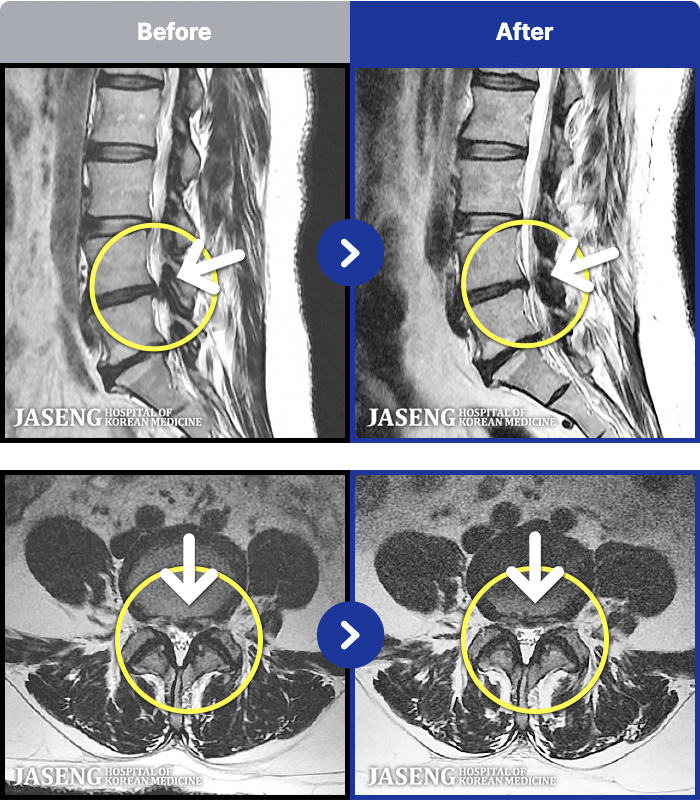

1,301 MRI ũ ʸ Ȯϼ.